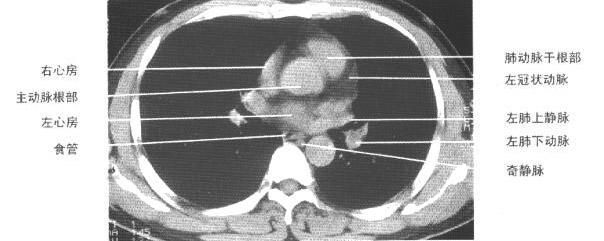

以下是引用jiangjing在2007-1-24 23:35:00的发言:[br]支持 增强扫描见右肺动脉干、左下肺动脉见充盈缺损。印象为:1、右肺动脉干、左下肺动脉栓塞。 2、左侧胸腔积液合并左肺下叶被动性肺不张。

以下是引用rjg199343在2007-1-24 23:22:00的发言:[br]增强扫描见右肺动脉干、左下肺动脉见充盈缺损。印象为:1、右肺动脉干、左下肺动脉栓塞。 2、左侧胸腔积液合并左肺下叶被动性肺不张。